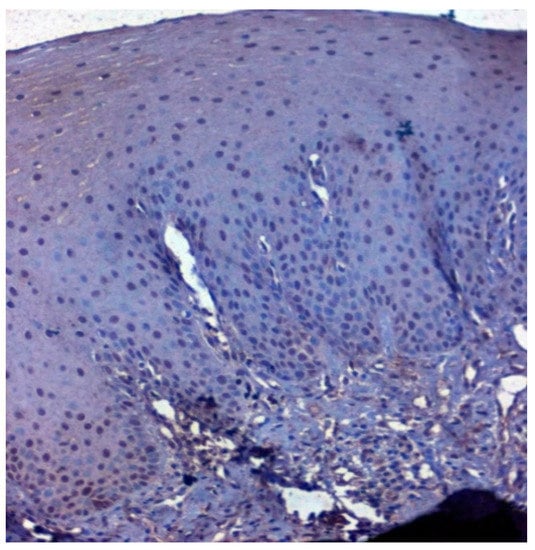

Figure 4.

IHC for CA 1 in normal samples (under 20× magnification).

Positive immunoexpression for CA 1 was found in 70.4% (88/125). Among the 40 patients with OSCC, CA 1 overexpression was found in 75% (30/40), and among the OSMF patients, CA 1 overexpression was found in 77.8% (56/72) compared to 15.4% (2/13) of normal, which was found to be statistically significant (p = 0.000; χ2 = 21.169) (Table 3). Based on different degrees of epithelial abnormalities, we found a statistically significant association (p = 0.025; χ2 = 11.144). Our results showed epithelial atrophy among the OSMF patients showing positive CA 1 overexpression. There was no significant association between CA 1 expression and degrees of inflammation, fibrosis and vascularity. Figure 4 shows the negative immunoexpression of CA1 in normal samples. Figure 5 shows the CA 1-positive immunoexpression in epithelial cells in OSMF samples, with cytoplasmic and nuclear positivity. In OSCC samples, CA 1 demonstrates strong cytoplasmic and nuclear positivity in malignant epithelial cells (Figure 6).